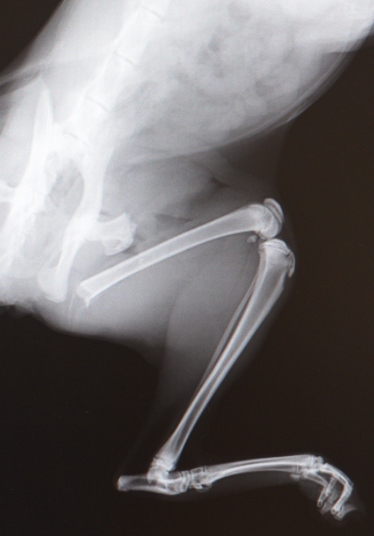

生後7ヶ月時に交通事故に遭い、大腿骨を骨折しました。しかも骨折端が皮膚を突き破り飛び出した状態で連れてこられました。開放性の骨折は汚れの付着があり、無菌的な処置が困難な場合が多く治りにくい症例になります。また、大腿骨の近位端は、大きな筋肉の付着部位である大転子があるため、大変大きな応力がかかり固定が困難な部分で、大変苦労する場合の多い症例です。手術は、ハイクロソフト水で充分に殺菌消毒して実施いたしましたので、深部の化膿など感染兆候は見られませんでしたが、皮膚の損傷が予想外に激しく縫合部位の癒合が遅れました。そして大変活発な性格の子猫で、退院後じっとして居られないらしく、『出して!出して!』と言ったとかで、オーナー様ご家族がケージから出して動かしてしまい、固定部位が固まるまで大変時間がかかってしまいました。一時はもうだめかと思うくらい心配しましたが何とか無事に固まってくれました。最初からずーっとハラハラさせられ、そして最後にホッとした症例です。

画像は、左の2枚が、事故後骨折端を戻して撮った画像、3番目が手術時、右の2枚が術後3ヶ月半で避妊手術時に撮影した画像です。しっかり固定できたので、ピンとワイヤーを除去して一件落着でした。